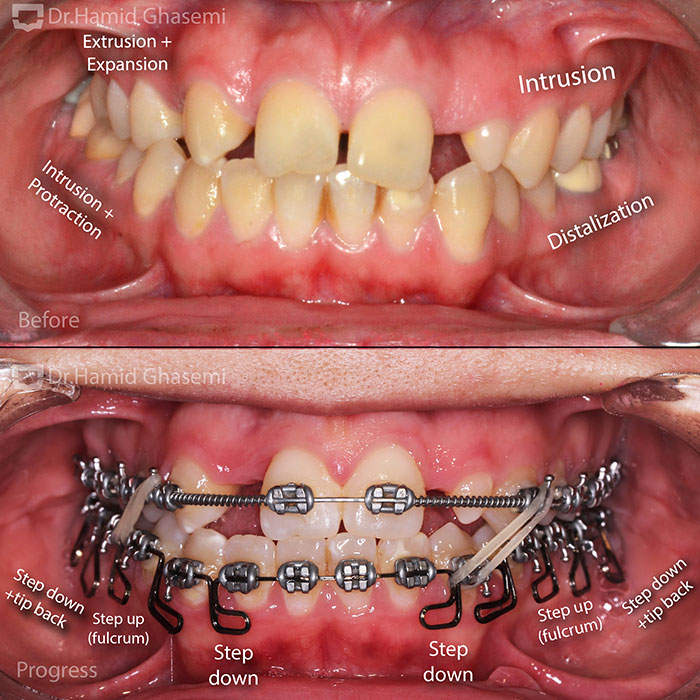

ارتودنسی مولتی لوپ؛ درمان تخصصی ناهنجاریهای فک و دندان11 آذر 1403 - 10:24 ق.ظ